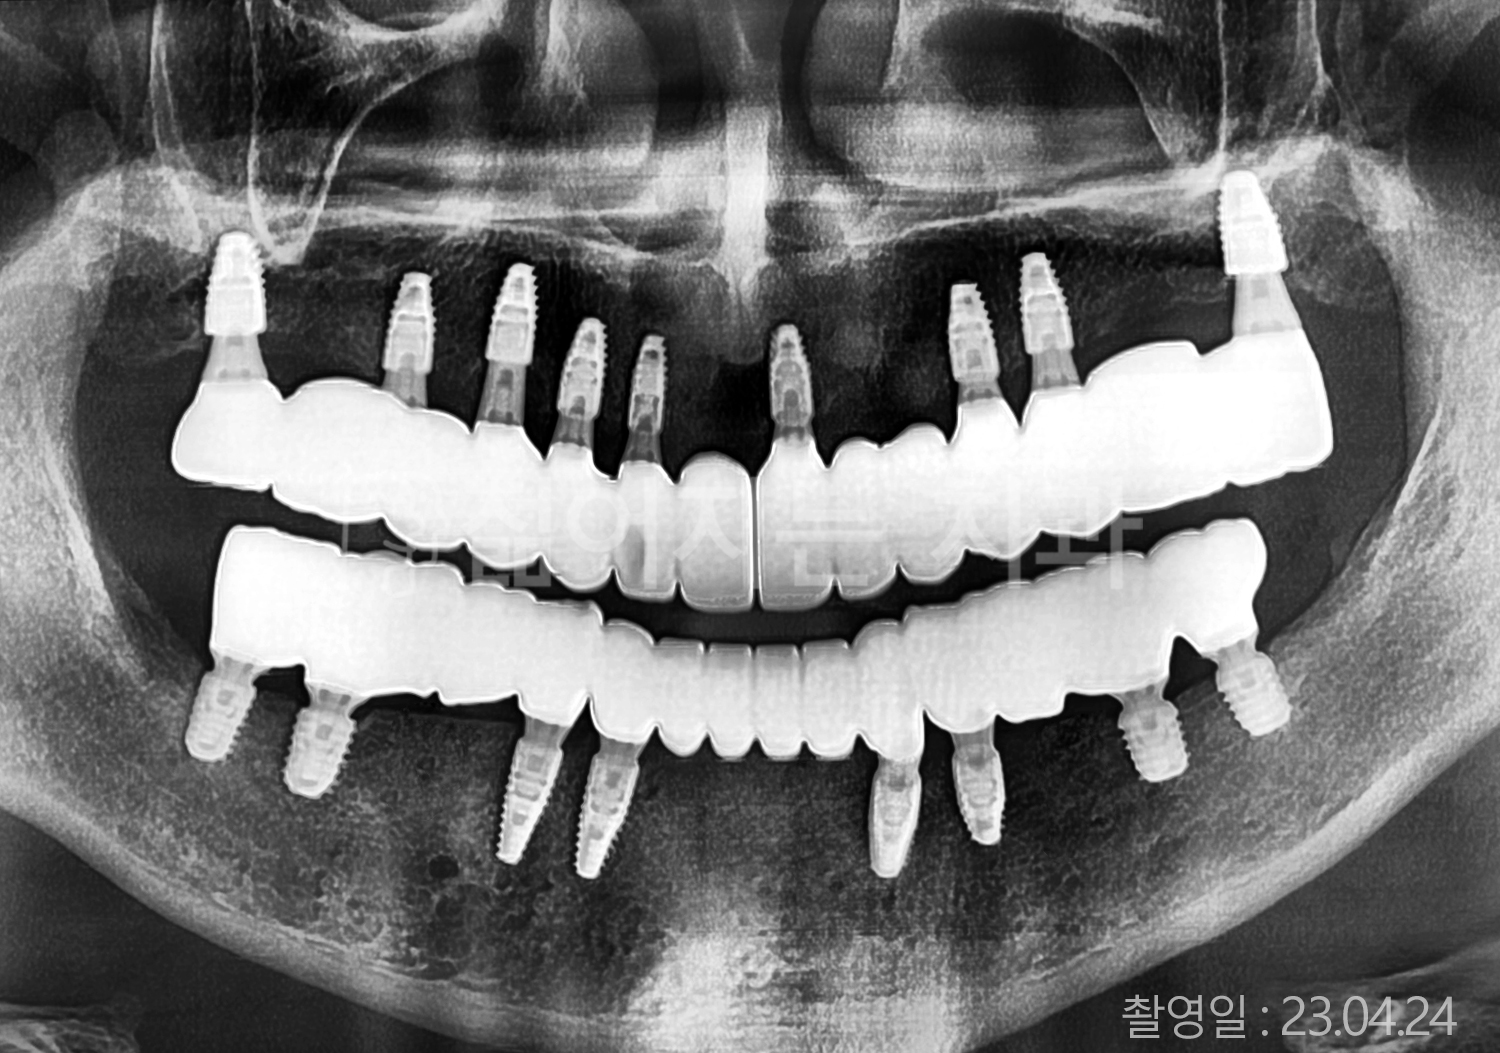

• 50대 고혈압, 고지혈증 전체치아 10개 이상 임플란트